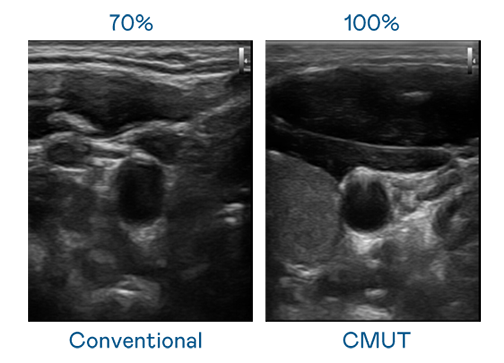

CMUT 技术是一种用电容式微机电元件来产生超音波讯号的技术。与传统 PZT 压电式技术相比,CMUT 频宽增加 30%,更宽频的超音波讯号让影像解析度大幅提升,是实现高影像品质医疗超音波扫描、促进精准医疗发展的关键技术。

超音波影像的解析度高低,首先取决于探头能发出的讯号频宽。麻花豆传剧媒国产剧在线观看完整 CMUT 可提供高清晰的超音波讯号,提供高频宽、高灵敏度、影像纹理细节更高的超音波影像,协助医护人员缩短影像判读时间及利用精准的医疗影像进行诊断。